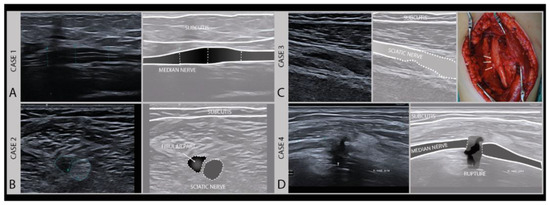

An important aspect for choosing the right therapeutic procedure and thus influencing the prognosis of a nerve injury, is to differentiate between patients with higher Sunderland grade intraneural damage or even the transection of a nerve versus a less severe lesion with preserved nerve continuity and good regenerative potential. To categorize a lesion as major or minor based on imaging (Figure 6), a few typical sonomorphologic signatures can be used, that include the fascicle swelling and hypoechoity of the nerve, the absence of a normal fascicular pattern, and the continuity assessment to detect partial or complete nerve severance with the presence of neuronal stump [28,29].

Figure 6.

Examples of different degrees of axonal damage. Case 1 (A): median nerve swelling following local trauma (fracture), fascicles intact, full recovery without surgery (Sunderland II). Case 2 (B): heterogeneous lesion of the sciatic nerve (peroneal part) of a 19-year-old boy after a scooter accident. Case 3 (C): sciatic nerve damage (Sunderland III) in a 9-year-old girl after a severe car-accident (high-frequency 9–18 MHz). (Intraoperative image kindly provided by PD. Dr. F. Lassner). Case 4 (D): iatrogenic median nerve lesion with loss of nerve continuity (Sunderland V) in a 53-year-old man after arthroscopy of the elbow joint (high frequency 19–24 MHz).

In pure neurapraxia, a Sunderland grade 1 and the least severe lesion, there are either no pathologic findings on ultrasound or just a mild swelling of the nerve with an intact fascicular pattern. A Sunderland grade 2 injury is slightly more severe with axonal damage, and also shows clearly enlarged cross-sectional areas of affected fascicles and nerves at the lesion site because of axonal swelling and edema. Higher grade damage like in patients with Sunderland grade 3 and 4 lesions shows a loss of the normal nerve architecture and echotexture with a disruption of the fascicular pattern and often sizeable hypoechogenic enlargement of the nerve. The more extensive the loss of the normal nerve architecture, the higher the chance that the nerve will develop intraneural fibrosis that hampers or prohibits recovery. For these lesions, a subdivision of the Sunderland system has been described by Millesi [30]. A Sunderland grade 5 lesion shows a transection of the nerve with a loss of nerve continuity. An overview of the nerve injury classification can be found here: https://en.wikipedia.org/wiki/Peripheral_nerve_injury_classification.

The early identification of these Sunderland grade 4 and 5 lesions is very important for predicting the outcome and the need for surgery [21,22]. High-resolution ultrasound allows this early categorization of lesions to guide surgical decision making [31]. Surgery is always indicated if nerve continuity is lost (i.e., Sunderland grade 5). In the case of a complete transection, the proximal and distal nerve stump will be separated, and as the regenerating axons in the fascicles have no guiderail for regrowth, they will form a stump neuroma as they sprout. A similar situation can occur if there is no gap, but so much intraneural damage that the nerve forms an internal “wall“ of fibrosis (i.e., Sunderland grade 4), through which axons cannot regrow (also see below). This will result in a large disorganized swelling at the lesion site, described as a neuroma in continuity.